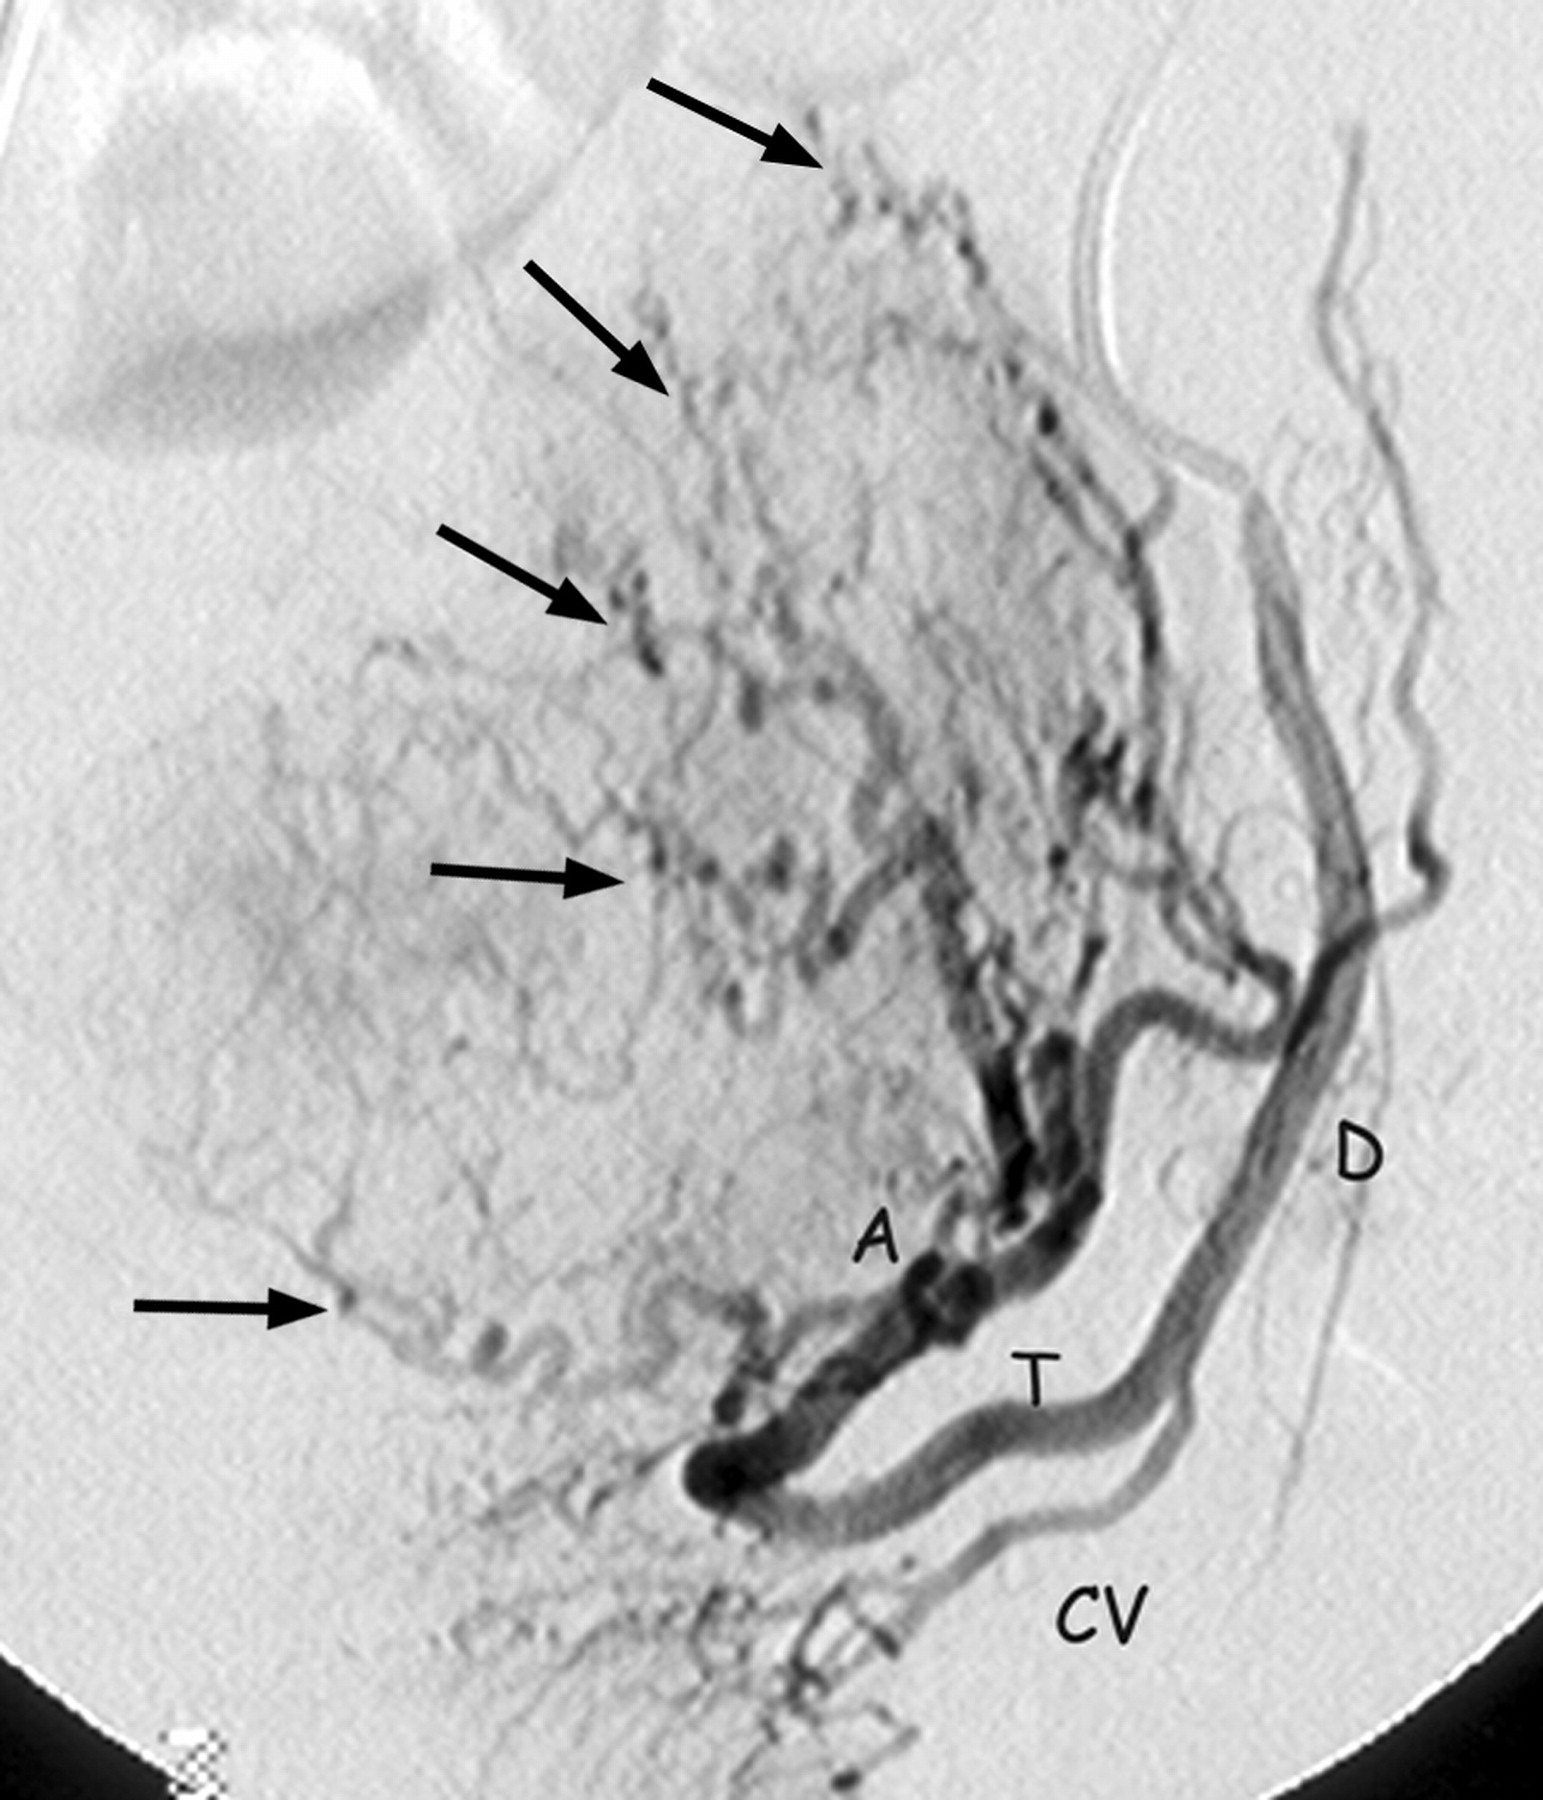

• Aorta -> Common Iliac -> Internal Iliac -> Anterior Division -> Uterine Artery